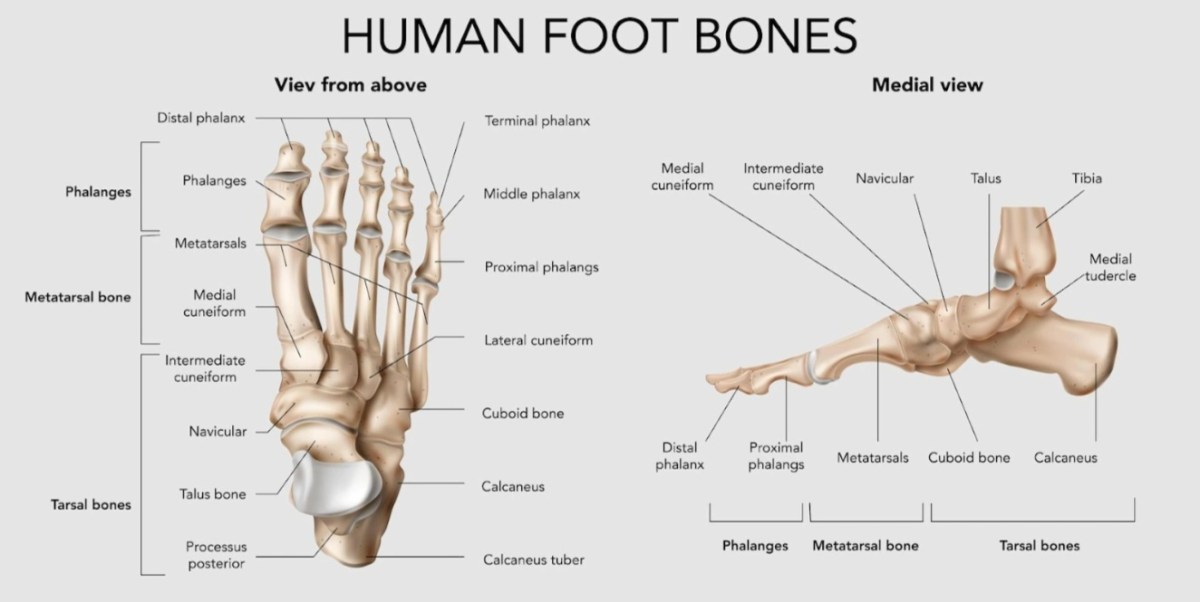

Telapak kaki terdiri dari 26 tulang yang saling terhubung, masing-masing memainkan peran penting dalam fungsi keseluruhan. Tujuh tulang tarsal di bagian belakang kaki, dan lima tulang metatarsal di bagian tengah kaki, berkolaborasi dengan luar biasa untuk memungkinkan kita bergerak. Mereka bukan hanya sekadar tulang, melainkan bagian dari sistem yang sangat terkoordinasi.

- Tulang Tarsal: Ini adalah tulang-tulang yang membentuk bagian belakang kaki, termasuk talus, kalkaneus (tulang tumit), navikular, kuboid, dan tiga tulang kuneiform. Talus menerima beban berat badan dari tulang kering (tibia) dan fibula, sementara kalkaneus memberikan stabilitas dan berperan penting dalam berjalan.

- Tulang Metatarsal: Terletak di bagian tengah kaki, tulang-tulang ini menghubungkan tulang tarsal dengan jari-jari kaki. Mereka membentuk lengkungan kaki, yang berfungsi sebagai peredam kejut dan membantu dalam propulsi saat berjalan atau berlari.

Ilustrasi Susunan Tulang Telapak Kaki

Mari kita gambarkan secara visual bagaimana tulang-tulang ini bekerja sama. (Perhatikan, ini adalah deskripsi visual, bukan permintaan gambar, ya!):

- Kalkaneus (Tumit): Tulang terbesar di kaki, membentuk dasar belakang kaki. Terletak di bawah talus, dan mendukung sebagian besar berat badan saat berdiri.

- Talus: Terletak di atas kalkaneus, membentuk sendi pergelangan kaki dengan tulang kering (tibia) dan fibula. Berfungsi sebagai penghubung antara kaki dan tungkai bawah.

- Navikular: Tulang berbentuk seperti perahu, terletak di sisi medial kaki, di depan talus. Berperan dalam membentuk lengkungan kaki.

- Kuboid: Terletak di sisi lateral kaki, di depan kalkaneus. Berkontribusi pada stabilitas dan gerakan lateral kaki.

- Kuneiform (Medial, Intermediate, Lateral): Tiga tulang kecil yang terletak di depan navikular, membentuk bagian tengah kaki. Berperan penting dalam membentuk lengkungan kaki dan mendukung gerakan.

- Metatarsal: Lima tulang panjang yang terletak di depan tulang tarsal, menuju jari-jari kaki. Masing-masing memiliki kepala, badan, dan dasar.

- Jari-jari Kaki (Falanges): Tulang-tulang kecil yang membentuk jari-jari kaki, memungkinkan gerakan dan keseimbangan.